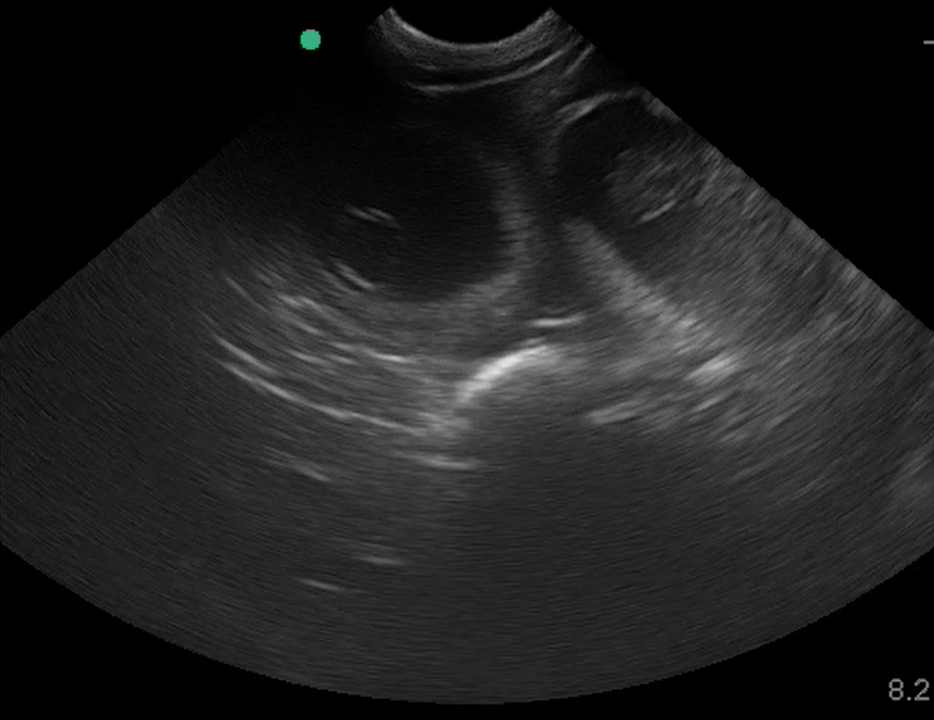

↑5/19撮影。エコー写真。

ちなみに5/19にエコー検査を行い、2頭の胎児が確認できました。